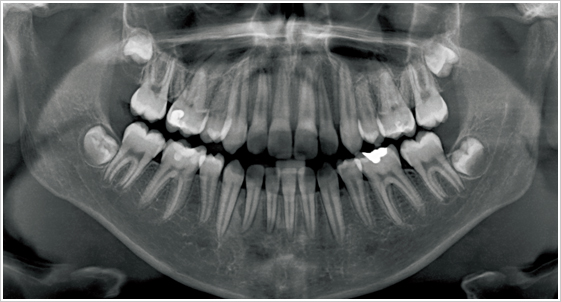

牙科專用的電腦斷層(Computed Tomography 簡稱CT)和一般的醫療電腦斷層的不同在於傳統牙科X光攝影所得的平面影像受到組織重疊的影響,無法觀察到內部的實際狀況,醫師常常因此造成誤判,為解決此問題,就需要牙科專用的3D電腦斷層攝影;若與傳統醫療電腦斷層相比較,牙科3D電腦斷層攝影有很多優點,如輻射劑量只有一般電腦斷層的1/50;採站姿或坐姿攝影,方便行動不便的患者;切片厚度一般醫療電腦斷層是 2.0 公厘,牙科3D電腦斷層則只有0.1公厘,解析度之高,比起一般醫療電腦斷層,影像當然來得細緻和精確。

電腦斷層掃描合成3D影像,術前準確模擬植牙角度及位置。

美國口腔顎面放射學會-AAOMR (The American Academy of Oral and Maxillofacial Radiology)2001 年研究文獻指出,從事植牙手術前醫師除了透過全口X光影像、根尖片影像觀察近遠心距離外,應再拍攝電腦斷層(CT)影像,藉由切面影像(Cross-sectional view)以事先評估出齒槽骨寬度、舌頰側的距離、骨質及組織的密度,才能提昇植牙手術的安全性。